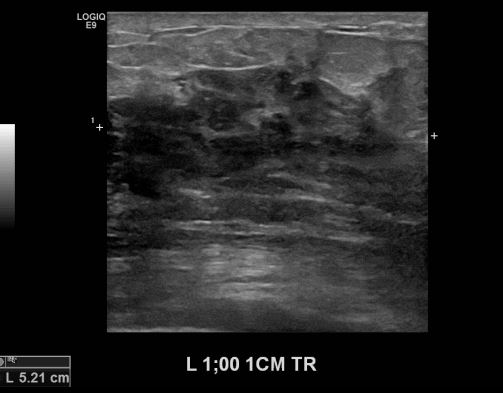

상기환자 좌측유방의 멍울로 내원하신 60대 여성분으로 본원 초음파상 좌측유방 1시 방향에서 1cm 떨어진 거리의 의심스러운 멍울 조직검사 시행하여 좌측 침윤성 유관암 진단 되었습니다.